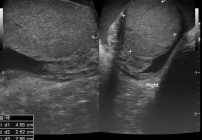

Badanie umożliwia ocenę jąder, najądrzy, osłonek jąder oraz struktur znajdujących się w obrębie worka mosznowego. Pozwala także wykryć obecność żylaków powrózka nasiennego, które mogą mieć znaczenie kliniczne i wpływać na dalsze postępowanie diagnostyczne lub lecznicze.

USG jąder jest jednym z podstawowych badań obrazowych wykorzystywanych w diagnostyce zmian w obrębie moszny. Dzięki niemu lekarz może lepiej ocenić przyczynę dolegliwości i zdecydować o dalszych krokach.